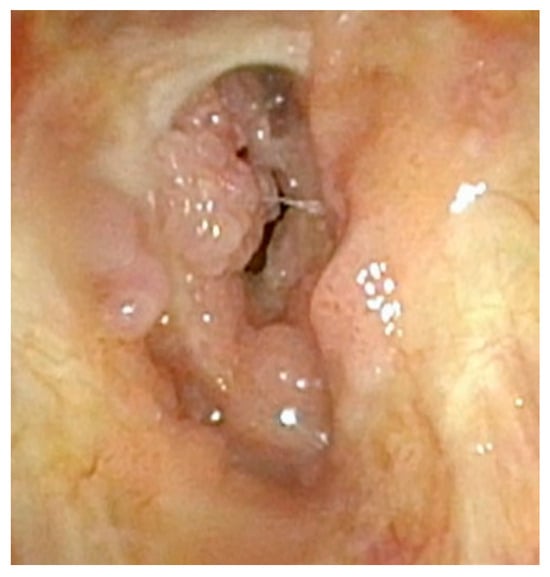

Although less common, care must also be taken not to disrupt the mucosa along the entirety of the posterior commissure. Should this occur, a patient is at great risk of developing posterior glottic stenosis (Figure 4). This should also be treated similarly to the anterior glottic web with midline lysis of the scar and injection of steroids, and dilation should always be performed in these cases (Figure 5). The combination of anterior or posterior glottic stenosis in the setting of a patient with papillomas can lead to significant airway obstruction and should be avoided in all cases with careful surgical attention (Figure 6).

Figure 6.

Significant posterior glottic web with papillomas causing near-complete obstruction of the airway.